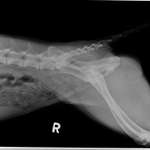

Ich habe das Gefühl, dass meine 8,5 Jahre alte Hündin immer engmaschiger Läufig und Scheinträchtig wird.

Ihre letzte Läufigkeit ging bis Ende Oktober, war dann die ersten zwei Dezemberwochen über Scheinträchtig und zeigt nun wieder die ersten Anzeichen einer Läufigkeit.